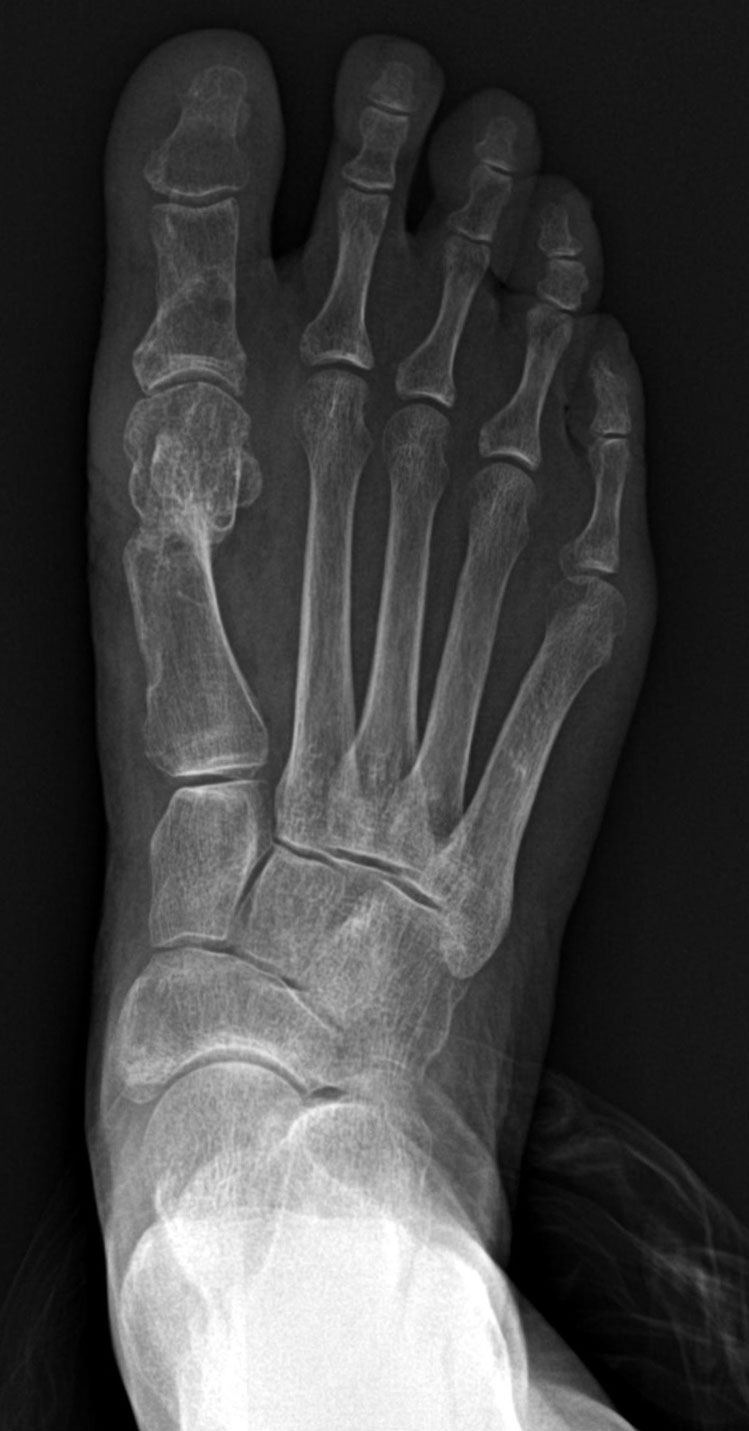

무지외반증 수술 전후

무지외반증 수술 전

무지외반증 수술 후(나사고정)

무지외반증 수술 후(나사제거)